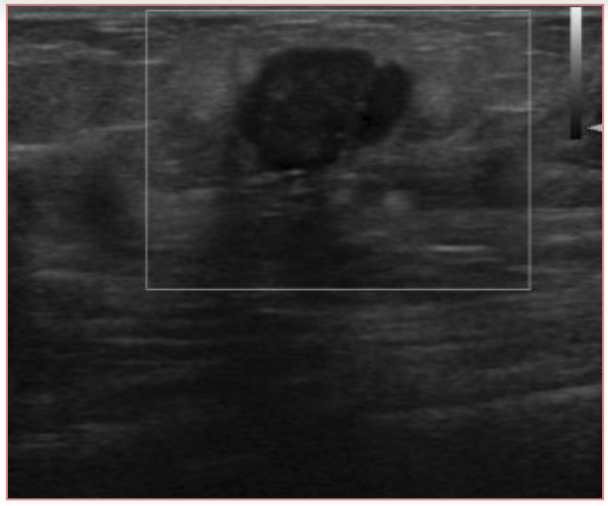

Ultrasound is well accepted as the most useful adjunct to mammography for the diagnosis of breast abnormalities. An exemplary ultrasound image of right breast of a patient is shown in Fig. 4. Ultrasound is most often used to assess palpable masses and nonpalpable masses that have been detected during screening mammography [20, 21]. Ultrasound may demonstrate malignancies and other masses that are not visible mammographically [22]. Ultrasound had an overall pooled sensitivity and specificity of 80.1% and 88.4%, respectively [11].